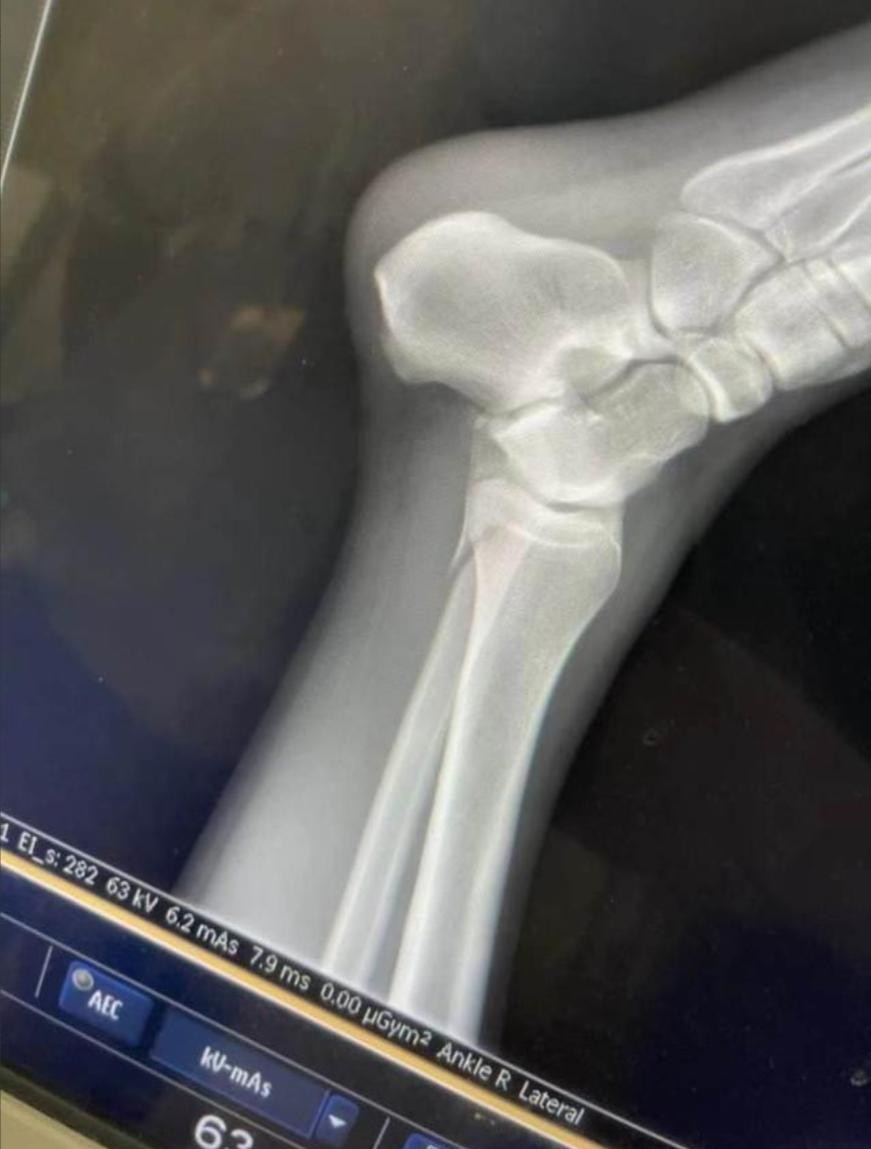

随后,记者对那位腿部受伤的女孩进行了采访。女孩透露,她的胫骨和腓骨同时断裂,伤势非常严重。更让人意外的是,她在搭乘救护车前往医院时的费用,并不是由节目组承担的,而是她和另一位受伤的小伙子平摊的。至于后续的治疗费用,节目组至今也没有进行任何赔付,所有的诊疗费用都是她自己掏的。